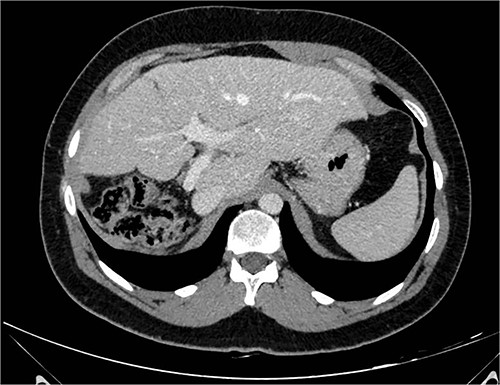

At 42 months follow-up liver function tests were normal and CT-scan performed 6 months, 1–2–3 years after surgery were negative for disease recurrence (Fig. 2).